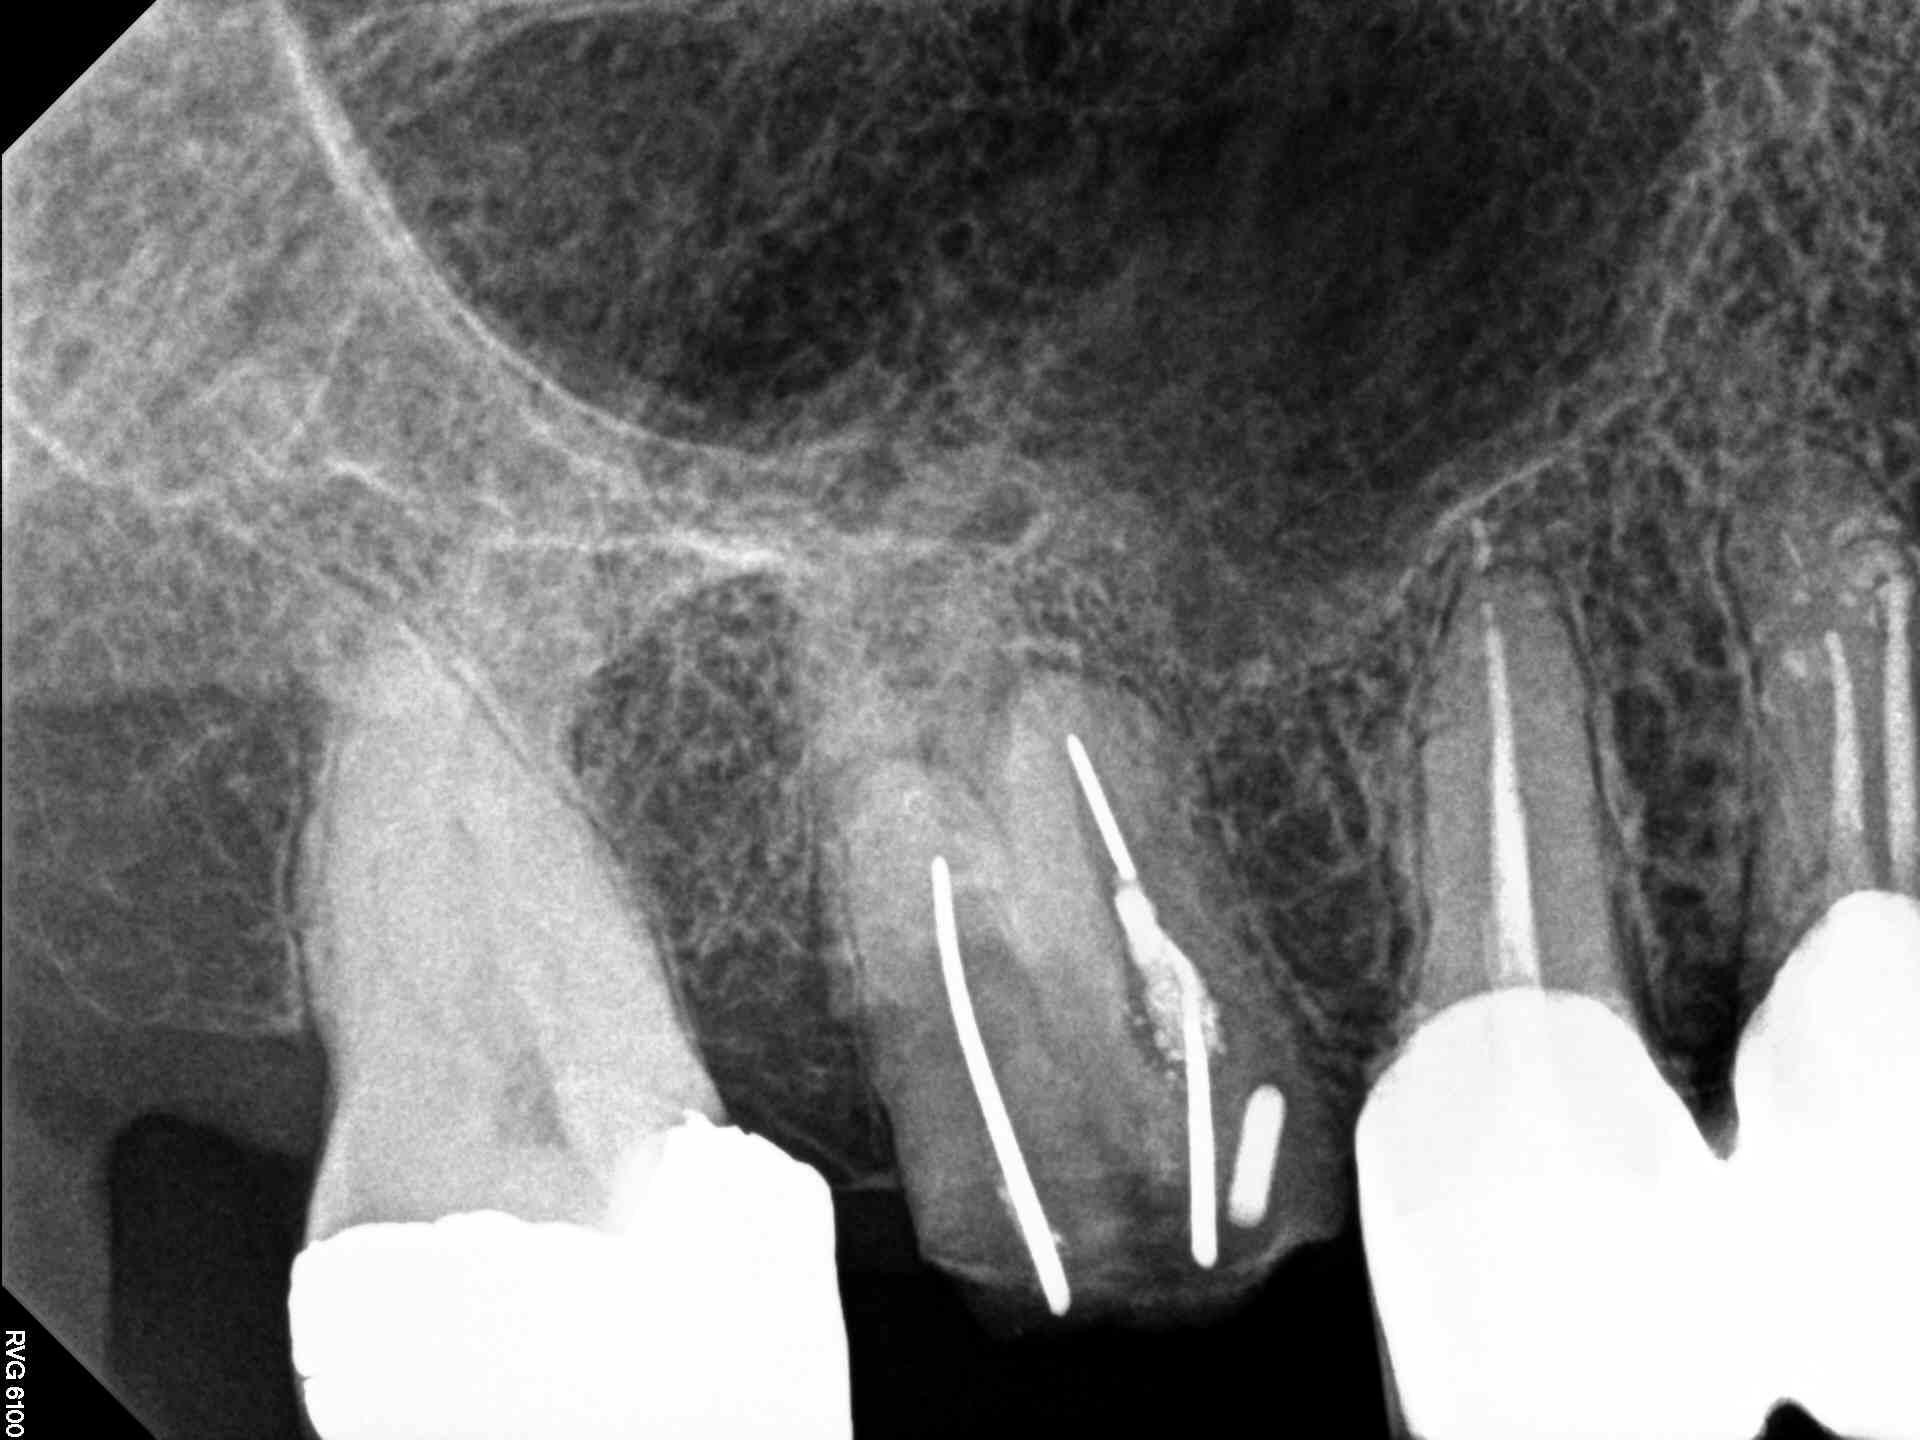

wallpaperaccess.comRoot Canal Surgery Photograph By Dr Armen Taranyan / Science Photo Library

fineartamerica.comsurgery armen